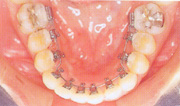

隐形正畸就是把矫治器全部安装于牙齿的舌侧面进行正畸治疗,因此也叫作舌侧正畸。这种正畸方法是从外面看不见矫治器,正畸治疗期间仍然可以进行正常的社交和职业活动。隐形正畸 —— 不知不觉中改变了牙齿排列,改变了面部形象。

成人舌侧隐形正畸治疗首先是由日本齿科医生发明并在临床应用,现在已经在发达国家逐渐普及。它是当前口腔正畸中技术含量最高、临床操做最复杂、但在治疗中美观效果最好的固定正畸矫治技术,因此既是当前临床正畸学研究的热点,也是固定矫治技术的高点。